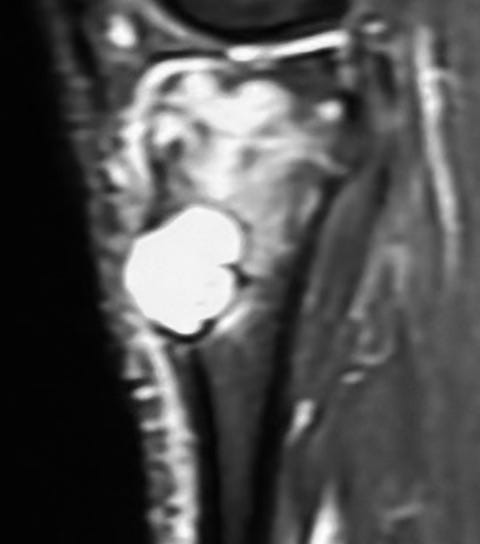

Case:

25-years old with knee pain.

X-ray shows an osteolytic lesion with a sclerotic rim - this is a benign lesion.

MRI shows marrow edema - this is now a “benign aggressive” lesion.

The lesion is partly T2 dark and shows a lamellated pattern of enhancement and is eccentric juxtamedullary.

A biopsy was done.

The findings are characteristic of chondromyxoid fibroma.